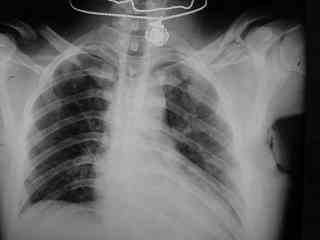

C> Postupil ko mne bolnoi s perelomom obeih kluchits, neznachitelny

C> pneumotorakx sleva.

Ну а за пневматораксом надо вести наблюдение, рентгенконтроль. При необходимости дренировать плевральную полость.

С пневмотораксом все понятно-дренировать плевральную польсть. А вот на счет ключиц действительно вопрос интересный, необходима золотая середина. Учитывая, что имеется повреждение грудной клетки, для улучшения активного дыхания необходимо будет выполнить остеосинтез обеих ключиц, накостный, реконструктивными пластинами.

Как справлялись с пневмотороксом?

Дренировали или пунктировали? Расскажите.

Pneumatorax hirurg punctiroval i lechil dalshe, operasia zanimala 1 chas 35 minut, ni bilo problem ossobih.